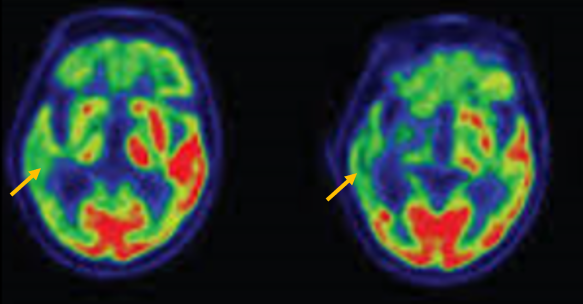

진행 핵상 마비는 대표적인 파킨슨 증후군 중의 하나입니다. 파킨슨병과 다른 점은 질병의 초기부터 중심을 잡기 어려운 체위 불안정이 나타나 자주 넘어진다는 것입니다. 파킨슨병의 경우 질병이 상당히 진행된 뒤에 체위 불안정이 나타납니다. 또한 진행 핵상 마비에서는 목 주위 근육을 비롯한 몸 중심 근육의 경축이 나타나, 목을 뒤로 젖히면서 걷는 모습이 보입니다. 그리고 눈의 운동을 조절하는 기능에 장애가 나타나 아래쪽을 바라보는 데 문제가 생겨 계단을 내려갈 때 어려움을 겪는 경우가 많습니다. 진행 핵상 마비가 의심되는 경우, 뇌 자기공명영상(MRI)에서 중뇌의 위축이 비정상적으로 심하게 나타나는 소견을 확인하거나, 뇌포도당 양전자 단층촬영(PET)에서 전두엽과 중뇌의 대사 기능이 저하된 소견을 확인하여 진단에 참고할 수 있습니다.

[진행핵상마비 환자의 뇌포도당 양전자 단층 촬영에서 확인되는 중뇌의 대사 저하 소견]

피질 기저핵 변성은 비대칭 증상을 두드러지게 보인다는 점에서 파킨슨병과 비슷합니다. 그러나 파킨슨병과 비교해 보았을 때 양측의 차이가 아주 심하게 나타난다는 특징이 있습니다. 질병 초기에 한쪽 손으로 동작을 하거나 계획된 행동을 하는 기능이 현저하게 떨어집니다. 간단한 손가락 모양도 따라 하지 못하는 현상을 보입니다. 또한 의지와 상관없이 제멋대로 움직이는 통제불능 손이 나타날 수 있습니다. 체위 떨림, 경축, 운동 완만과 같은 파킨슨병에서 볼 수 있는 증상들은 피질 기저핵 변성에서도 관찰될 수 있습니다. 또한 집중력 장애, 수행 장애, 이름 대기나 언어의 유창성이 떨어지는 등 전두엽 및 두정엽과 관련된 인지 장애가 나타납니다. 피질 기저핵 변성은 뇌 자기공명영상(MRI)에서 증상의 반대쪽 전두두정엽의 위축 소견이 특징적으로 나타납니다. 뇌포도당 양전자 단층촬영(PET)에서도 전두엽, 뇌기저핵에 비대칭적인 대사 저하의 소견이 보입니다.

[피질기저핵 변성 환자의 뇌포도당 양전자 단층촬영에서 확인되는 비대칭적인 대사 기능 저하]